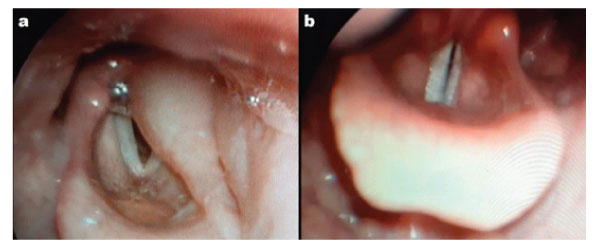

Flexible fibre optic Naso-pharyngoscopy revealed a gross oedema of the left hemilarynx that extended from the epiglottis to the left ventricular cord and left arytenoid cartilage. (Figure 1-a). Vocal cords were partially covered by the oedema. Nasopharynx and oropharynx were slightly edematous as well. Cervical CT scan found: a left pharyngo-laryngeal wall thickening, extended on 6 cm from cavum to glottis, with ipsilateral upper internal jugular lymphadenopathy with central necrosis and perilesional edema (Figure 2). Lab investigations showed hyperleukocytosis with 12000/mm3 and high C-reactive protein (CRP): 372 mg/L. Erythrocyte sedimentation rate (ESR) was raised at 49 mm/h. A fine-needle cytopuncture with histopathological examination revealed ganglionic lymphoid parenchyma with foci of eosinophilic necrosis surrounded by a palisade of lymphocytes, without epithelioid or giant cells, consistent with histiocytic necrotizing lymphadenitis of Kikuchi-Fujimoto (Figure 3).

The patient received intravenous corticosteroids (prednisolone 15 mg/kg per day for 5 days) and intravenous antibiotics (association of amoxicillin and clavulanic acid 3g per day for 7 days). Dyspnea and dysphonia disappeared within 24 hours of treatment. Flexible fibre optic Naso-pharyngoscopy at the third day showed complete resolution of edema (Figure 1-b). Lymphadenopathy decreased in size gradually and had fully disappeared at the 3 weeks follow-up. Regular surveillance for the past 11 months showed a complete recovery and no sign of recurrence.

Figure 1: a) Flexible fibre optic Naso-pharyngoscopy on admission showing oedema of epiglottis and left arytenoid cartilage. b) Flexible fibre optic Naso-pharyngoscopy at day 3 of treatment, showing complete resolution of the pharyngo-laryngeal edema.